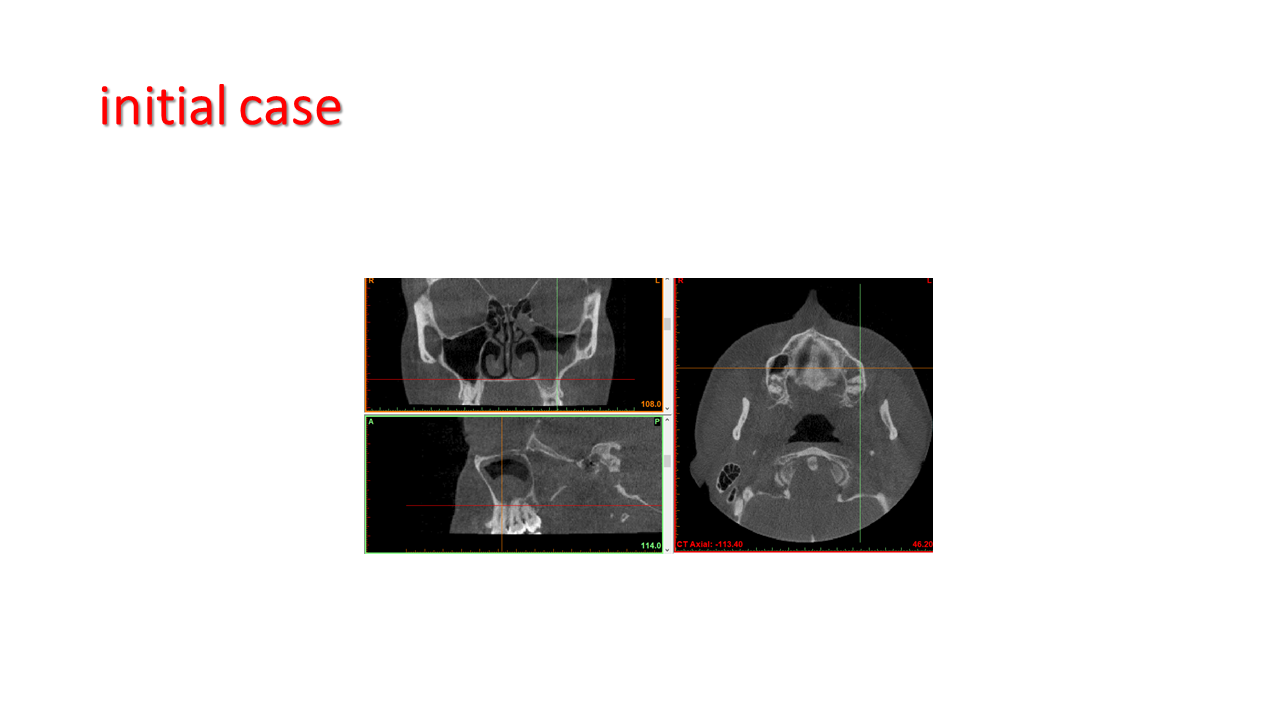

FESS Case Review and Radiologic Analysis (30.09.2016)

Case-based presentation focused on pre- and postoperative imaging in functional endoscopic sinus surgery (FESS). Includes anatomical landmarks, surgical variations, sinus pathology, and technique evaluation. Delivered by Dr. Levon Galstyan at AAOMFS.